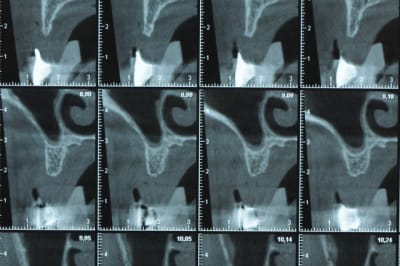

Une petite étude de ton cas D57

Sous réserves bien sur de voir l’animal en vrai

Les zones exploitables radiologiquement parlant:

Coupes implant

2,3 40100

4,96 35130 avec sinus lift mais difficile

5,25 35150

6,02 35130

6,78 35115 après réduction de hauteur de crête

7,26 35115 après réduction de hauteur de crête

8,51 35150

10,43 40115 ou 50115

11,10 40115

Ce qui nous fait 9 implants possible évidement avec un comblement de sinus on augmenterait encore les zones implantable mais ce n’est pas le but recherché, avec 8 (4+4) il doit être possible de faire une belle barre support de complet